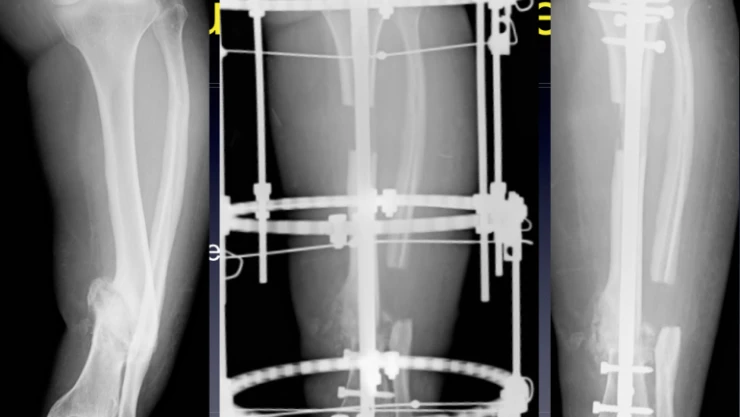

Çalışma ve Sosyal Güvenlik Bakanı Vedat Bilgin, kemik içi implantta her implant için 90 TL olarak ödenen tutarının 750 TL'ye çıkarıldığını açıkladı.

Bakanı Bilgin, sosyal paylaşım sitesi Twitter hesabından yaptığı paylaşımda, “Genel Sağlık Sigortalılarımıza Sosyal Güvenlik Kurumu tarafından ödenen tutarlar Sağlık Uygulama Tebliği kapsamında arttırıldı. Bu kapsamda vatandaşlarımıza kemik içi implantta her implant için 90 TL olarak ödenen tutar 750 TL’ye çıkarıldı” ifadelerine yer verdi.